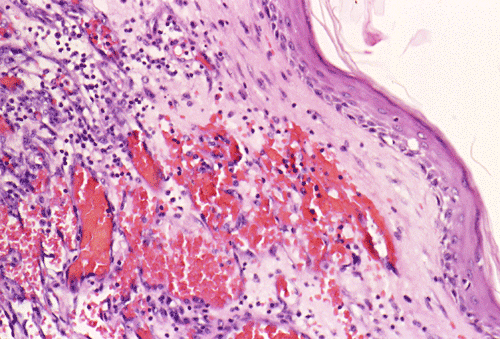

Panel A, B and F are taken from the dermal-epidermal junction. Panel B, C, D, and E are taken from the same area. Panel F, G, H, and I are taken from the same area

The tumor appears to be centered on the dermis and does not involve breast parenchyma in the sections examined A (not shown). On low-magnification (Panel A, B and F), the lesional tissue is a highly cellular and vascular tumor in the dermis. The large areas of hemorrhage ("blood-lake") and dilated vascular channels (Panel A, and F) probably correspond to the "red nodules and yellow patches" on physical examination. Although the tumor extends deeply into the subcutaneous tissue (not shown here), there is no evidence of invasion in to the epidermal layer (Panel A, B and F). The histology of this tumor varies in different areas. In some areas, it appears as a densely packed spindle cell tumor with exuberant and irregular and anastomosing vascular channels (Panel B, C, and D). The endothelial cells protrudes into the vascular channels and had enlarged, hyperchromatic nuclei with  prominent nucleli. In another area, the lesion contains numerous ectactic and anastomosing vascular channels (Panel F, G, H, and I). Pleomorphic changes are also prominent in the vascular cells in these areas. On immunohistochemistry, the tumor cells are immunoreactive for CD31, CD34 (not shown).